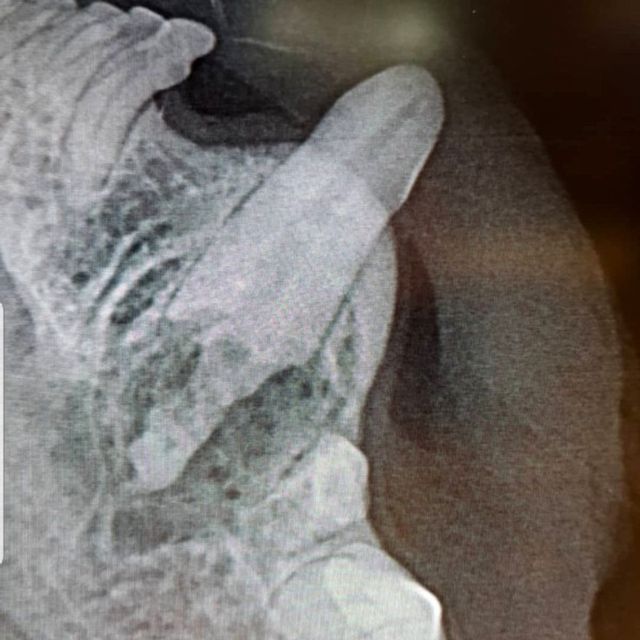

Etter hvert vil slik betennelse utvikle seg fra å være en overflatisk betennelse i tannkjøtt til en dypere betennelse mellom tanna og tannbeinet. Dette er svært smertefullt for dyret, og tanna vil løsne. I de fleste tilfeller vil den eneste løsningen for en slik tann være å trekke tanna. Dette vurderer dyrlegen din ved å gjøre en grundig undersøkelse av tanna og tannkjøttet, og ved å ta røntgenbilder av tanna. Dette må gjøres når dyret er i narkose.

Ved et tannrens hos oss blir først munnen skyllet med et antiseptisk middel. Deretter blir belegg og tannstein fjernet med ultralyd, før en fjerner tannstein under tannkjøttranden med en spesialskrape. Det er svært viktig at all tannstein - også den mellom og på baksiden av tennene fjernes. Deretter blir tanna polert glatt. Dette er viktig ettersom skraping av tannstein vil føre til riper i emaljen som bakterier og belegg vil få godt feste i om det ikke poleres bort. Så blir hver eneste tann undersøkt med en probe for å sjekke at det ikke er lommer i tannkjøttet eller problemer med røttene. Hos oss er også røntgenbilder av alle tennene inkludert i prisen for tannstell.

En tann som er brukket inn til pulpa, der nerven og blodkarene til tanna ligger, er svært smertefullt for hunden. Den blottede pulpaen vil også være inngangsport for bakterier, og vil ofte føre til tannrotsbyller. En slik skade kan i noen tilfeller repareres med rotfylling, dette må vurderes etter undersøkelse og røntgen av tanna. Dersom dette ikke er aktuelt må tanna trekkes.

Ofte er røntgenbilder den eneste måten å sikkert vurdere om en tann må gjøres noe med eller ikke. Hos oss er røntgenbilder av alle tennene inkludert i prisen ved tannrens.

Det er også viktig med røntgenbilder av aktuelle tenner både før og etter trekking, for å sjekke hvordan røttene ligger og ser ut - og for å kontrollere at en har fått med seg alt. Nødvendige røntgenbilder tatt i forbindelse med tanntekking blir det fakturert for.